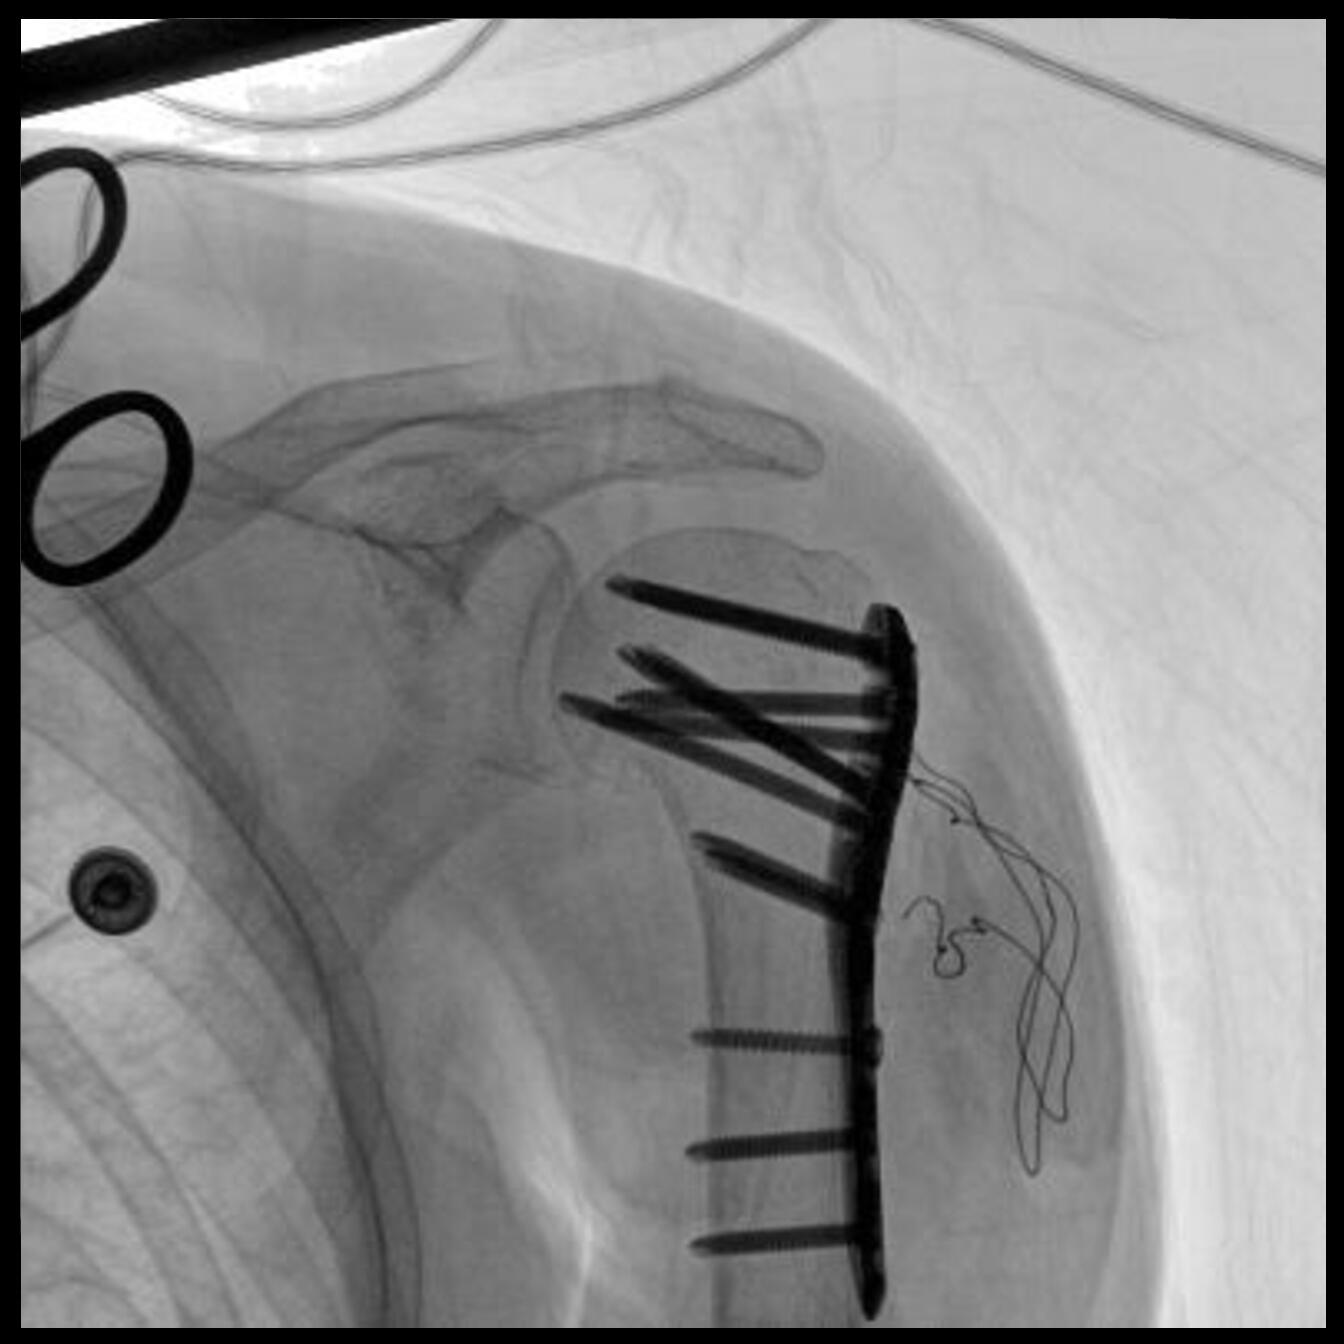

PLX118F-Plus配备了两种平板尺寸,大尺寸动态平板探测器成像面积较传统平板探测器提升了25%以上,在视野需求大的手术中,便于医生更好定位病灶点,规划手术方案,减少因视野范围不足而多次透视、点片造成的不便,不仅提高了手术效率,也减少了辐射剂量。